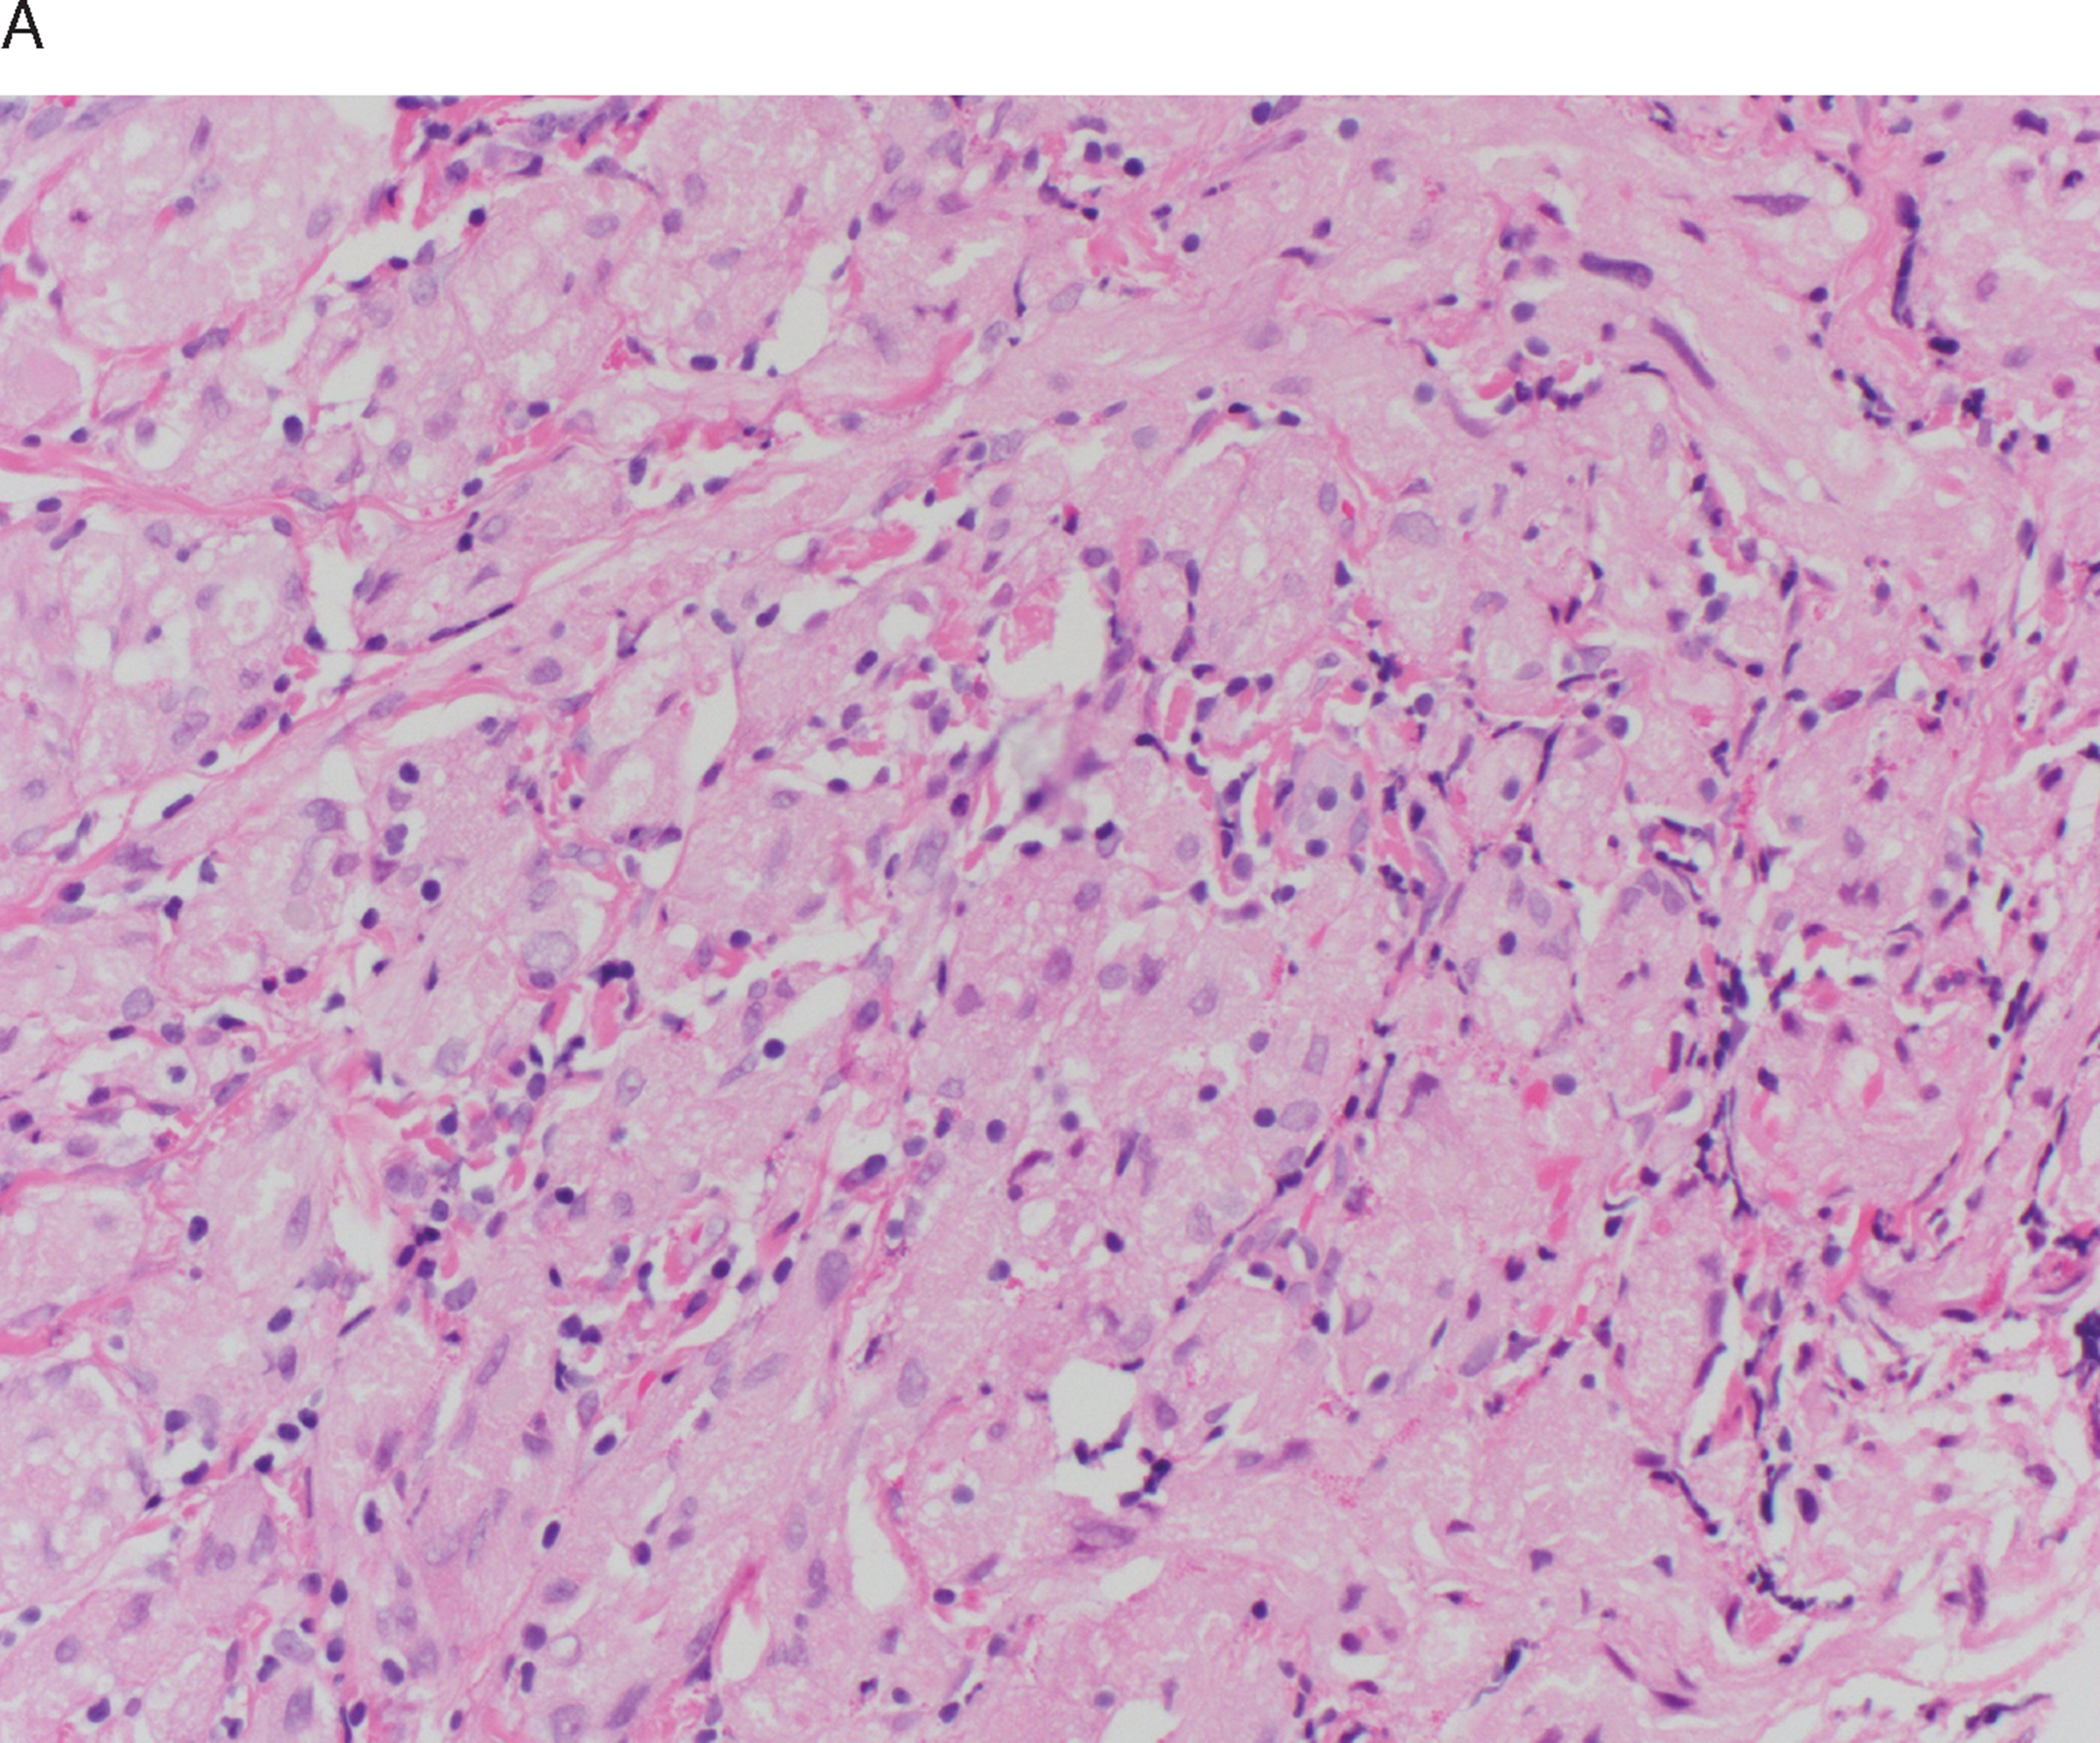

Neoplastic diseases of the small and large intestines (Chapter 27